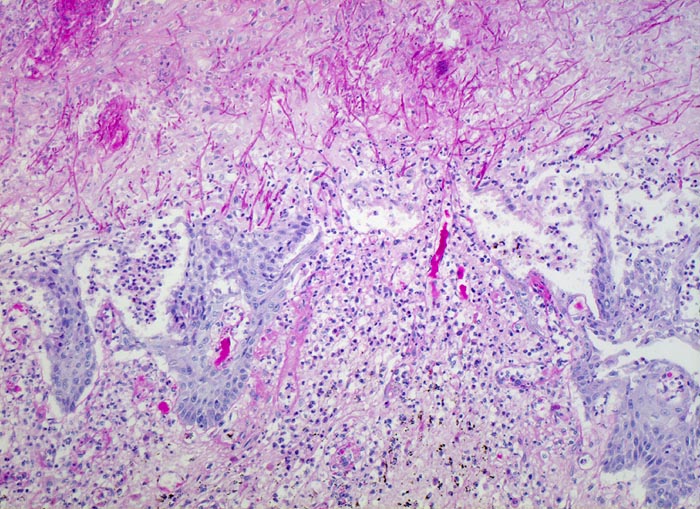

Endoskopisch finden sich abstreifbare weissgelbe krümelige Plaques, welche keine Prädilektionsstelle zeigen. Die Schleimhaut kann erodiert oder ulzeriert sein. In Klumpen von nekrotischen Plattenepithelzellen lassen sich mikroskopisch oft Sporen und Pseudohyphen nachweisen. Die Pseudohyphen wachsen oft senkrecht zur Epitheloberfläche. Besonders gut sichtbar werden die Pilze in der PAS oder Grocott Färbung. Zusätzlich besteht eine aktive Ösophagitis mit Infiltration der oberflächlichen Plattenepithelschicht durch neutrophile Granulozyten. Zahlreiche neutrophile Granulozyten in einem Ulkus weisen auf eine Soorösophagitis. Bei viral bedingten Ulzera (Herpes, CMV) prädominieren Makrophagen.

• Die Pseudomembran über der ulzerierten Schleimhaut setzt sich zusammen aus einem dichten Netzwerk PAS positiver Soorpseudohyphen und ovale aussprossende Sporen, nekrotischem Plattenepithel, Fibrin und neutrophilen Granulozyten.

• Die Pseudohyphen infiltrieren das Plattenepithel.

• Im Unterschied zur Aspergillose dünnere Pseudohyphen ohne echte Verzweigungen und zahlreiche Sporen.